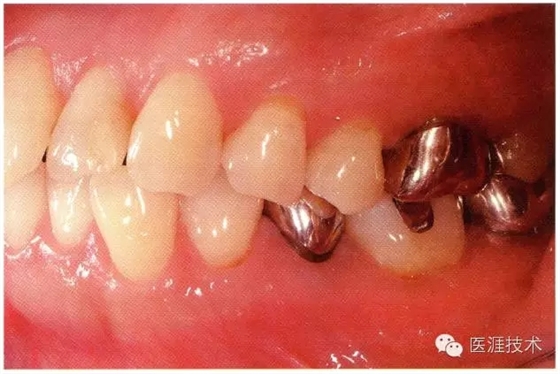

55歲牙周炎男性的臨床照片

640.webp (16).jpg

55歲男性抽煙患者(1天20支、抽煙35年)。菌斑控制得不好。通過牙周探診,全頜有4~9mm的牙周袋,有1~3度的根分叉部病變。通過X光片觀察,上頜前牙中度牙槽骨吸收,其他地方有中度牙槽骨吸收。受吸煙影響,牙齦纖維性肥厚,呈紅黑色。牙齦幾乎沒有浮腫和發(fā)紅,所以這個(gè)病例是從外觀上無法預(yù)測(cè)病癥嚴(yán)重程度的病例。